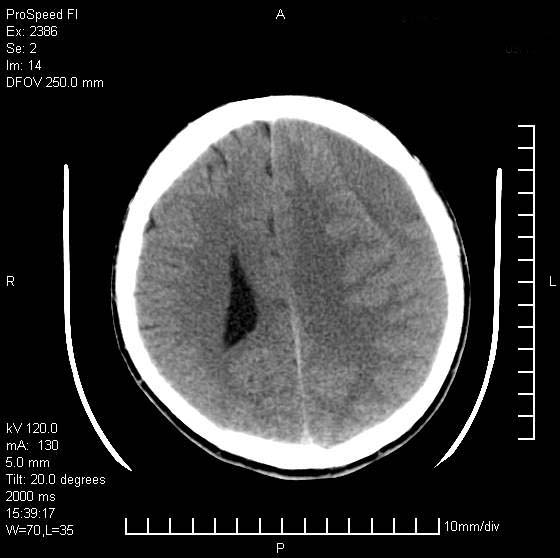

以下是引用天南地北在2007-9-19 18:43:00的发言:[br]典型慢性硬膜外血肿[br][br][本贴已被 天南地北 于 2007-9-19 18:44:11 修改过]

以下是引用曼一拍在2007-9-20 11:06:00的发言:[br]支持慢性硬膜下血肿.[br]慢性硬膜下积液:血肿有包膜,ct值稍高于脑脊液,增强可有染色。不典型者血肿可多呈梭形.是硬脑膜与蛛网膜之间的潜在腔隙内的血肿。[br]鉴别:[br]1\\硬膜外血肿:是颅脑外伤后脑膜或板障内血管破裂,血液在颅骨与硬膜之间积聚所致.通常是脑膜动脉破裂,也可因静脉窦破裂或颅骨的板障静脉出血,发生于外伤的着力部,常与颅骨骨折并存。脑膜动脉出血则急,若是板障静脉出血在则可有慢性。[br]2\\硬膜下积液:(硬膜下水瘤)[br]是由于蛛网膜破裂,脑脊液经蛛网膜破口进入硬膜下腔不能回流。或水肿阻塞而形成。[br]ct表现:颅骨内板下方新月形低密度区近似脑脊液密度;占位效应清,周围无脑水肿。[br]